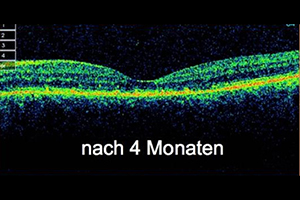

Beispiel: Feuchte altersbedingte Makuladegeneration

68-jähriger Patient mit zunehmender Sehminderung seit 6 Wochen auf 0,3 (30%). Nach 3-maliger Anti-VEGF Therapie Rückgang des Ödems und Besserung auf 0,5

nach der Behandlung